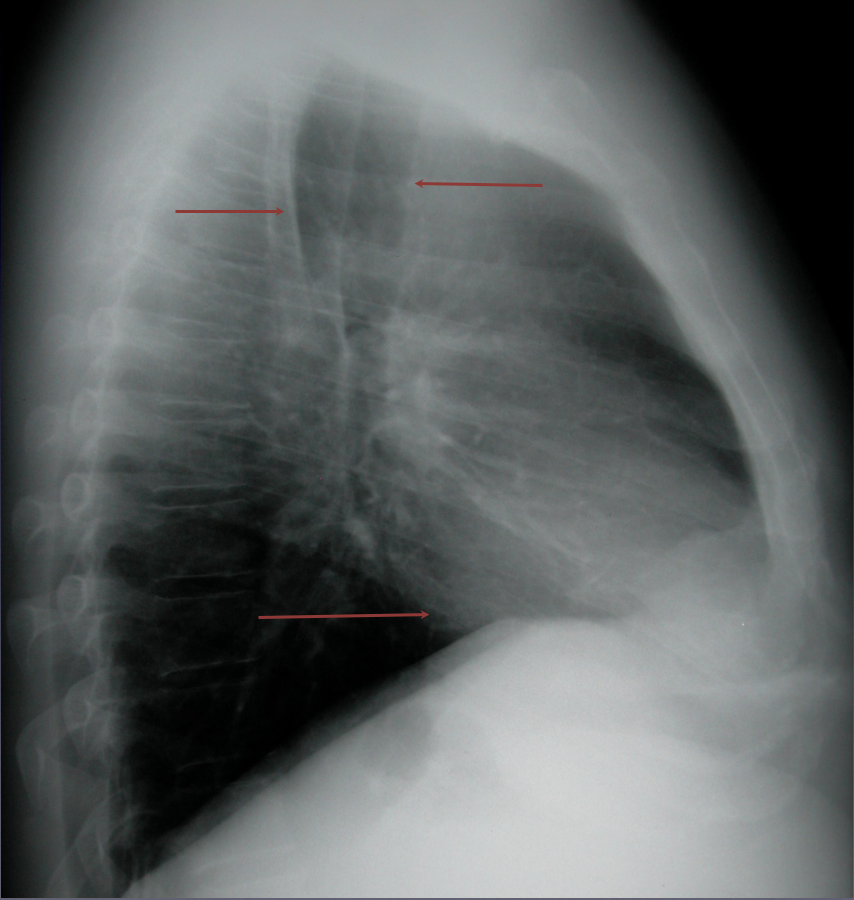

13

Go

A

The retrosternal and retrocardiac spaces should be dark on a lateral CXR.

-If they are not, disease is present

Normal CXR